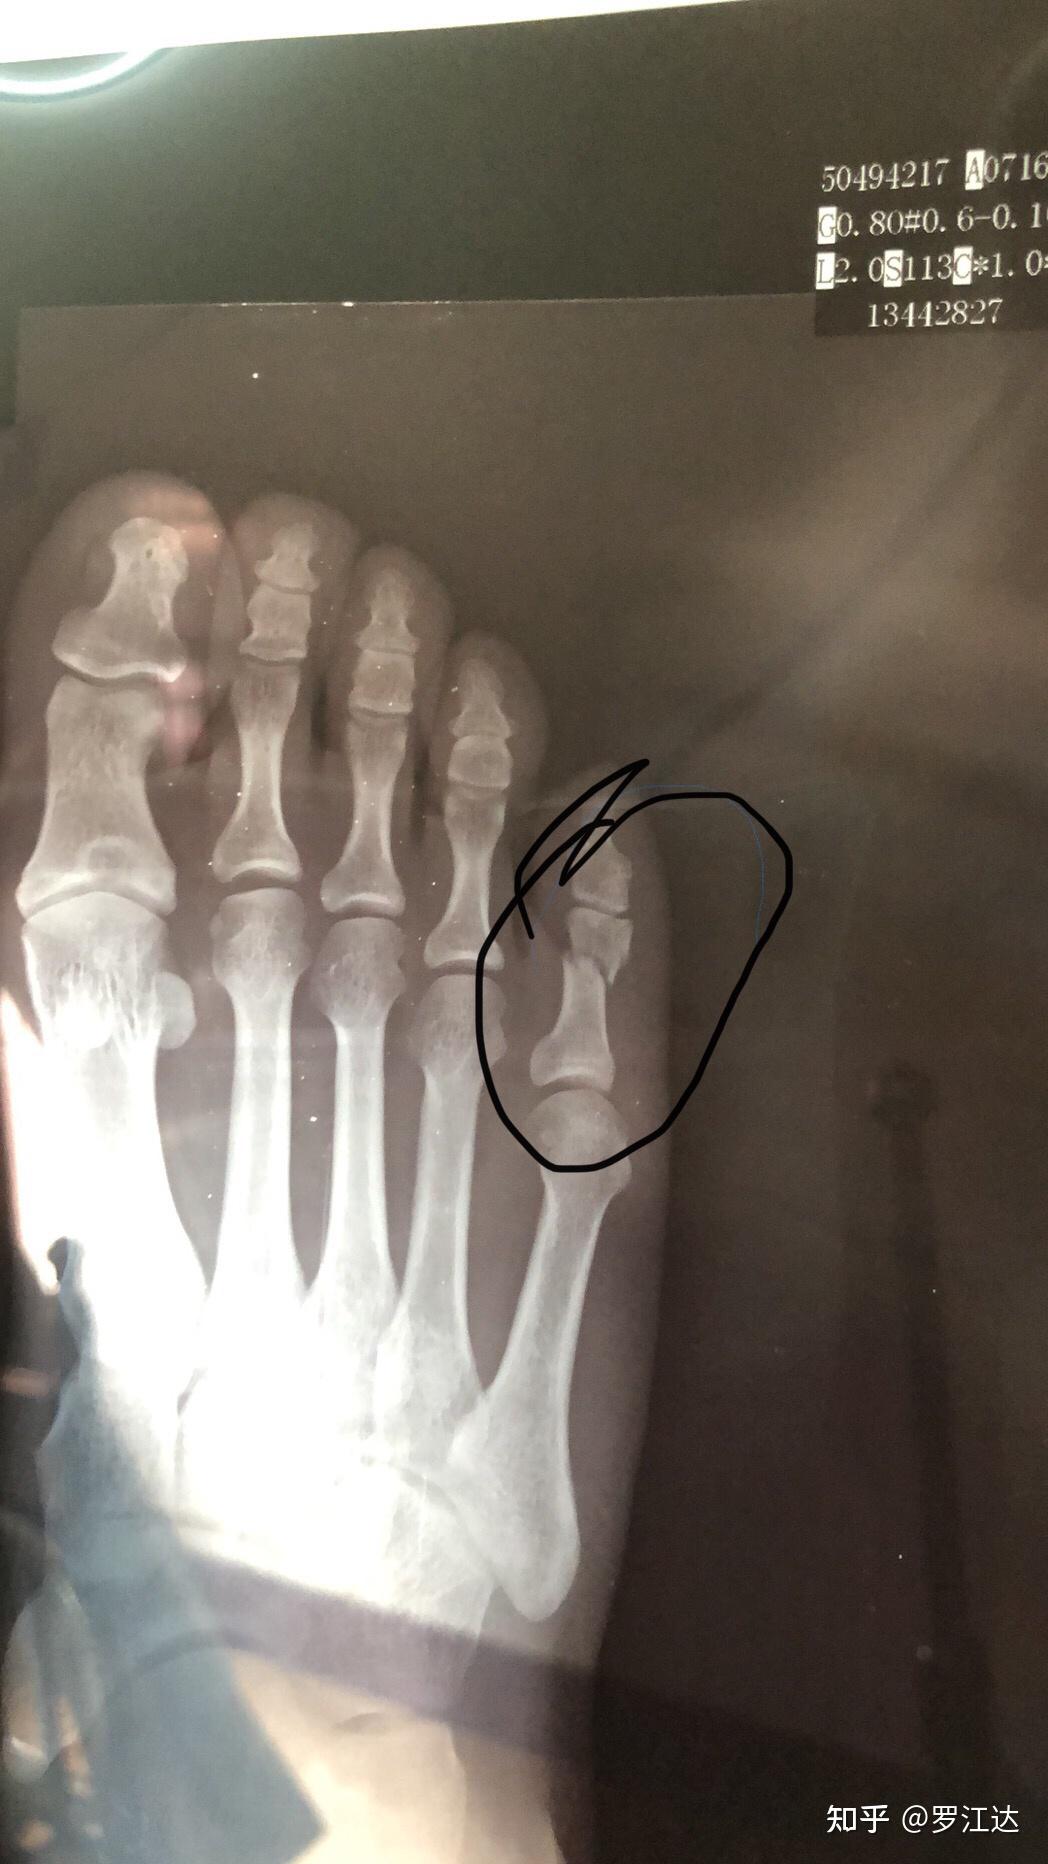

- 右脚小脚趾远端骨折能凭工伤十级吗图片尺寸1048x1864

- 脚趾骨折,哪位帮看看用不用治疗图片尺寸992x744